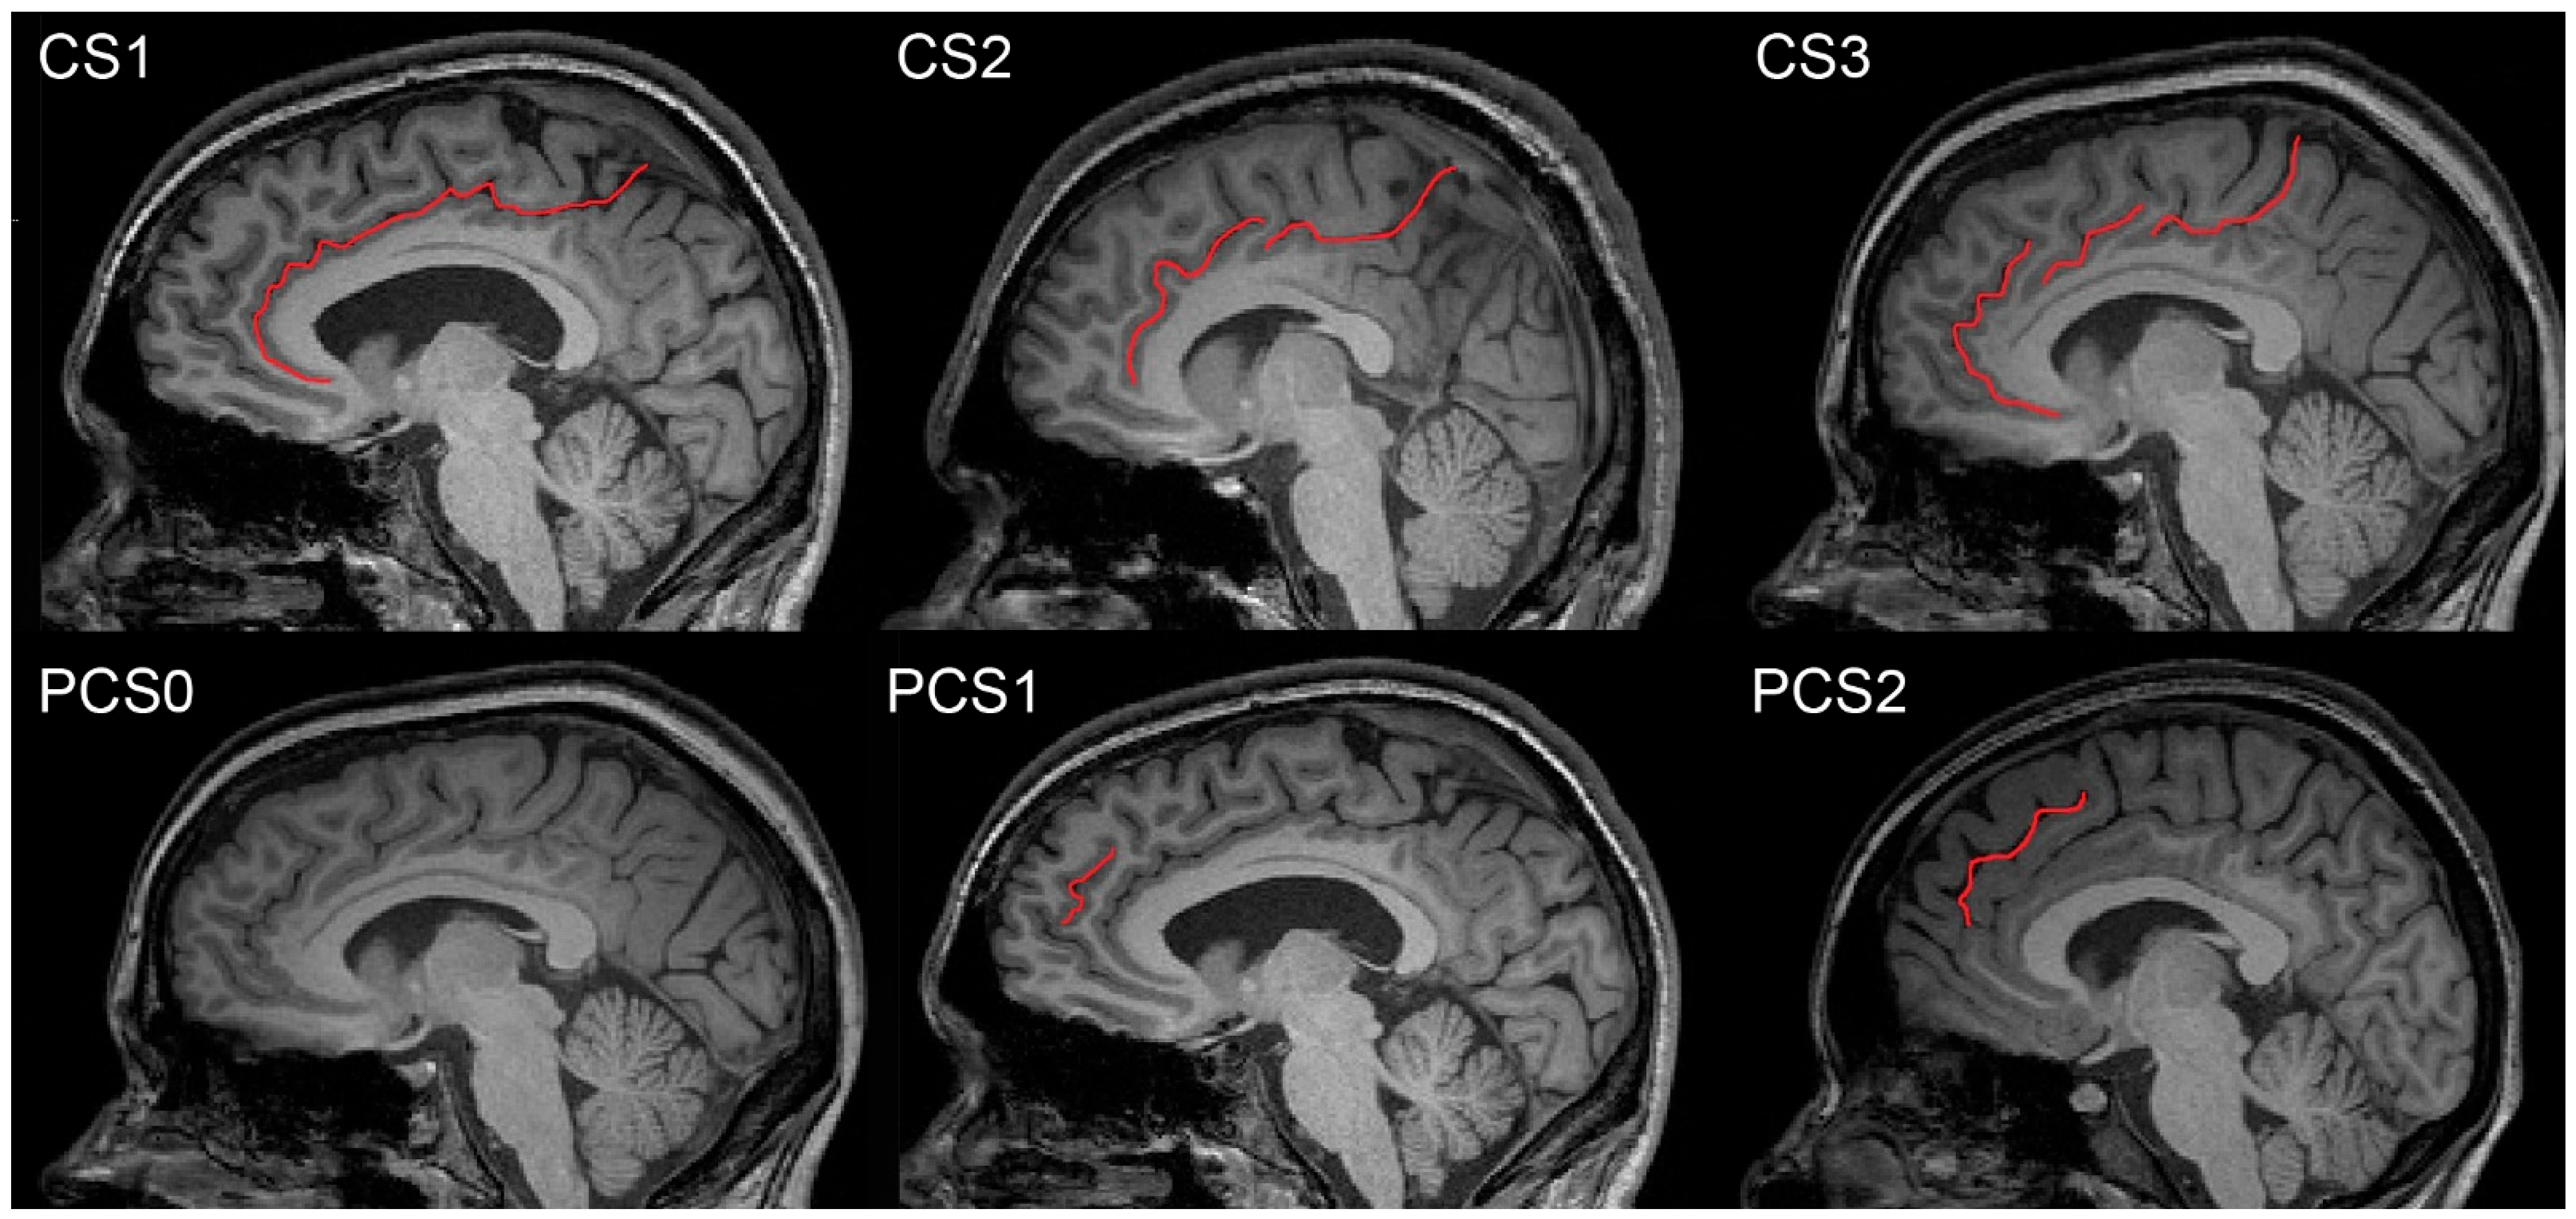

2.4.1. CS and PCS Manual Delineation and Morphology Considerations

2.4.2. Description of CS and PCS Parcellation and Its Nomenclature